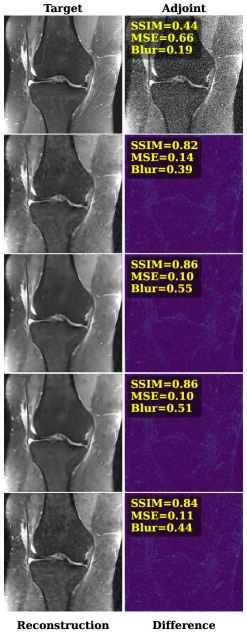

Comparison to Other Methods: Figure 4 shows a visual comparison of the adjoint reconstruction, MoDL, E2E VarNet, SRDenseNet, and the investigated CDL-𝚲\boldsymbol{\Lambda} using K=64K=64 filters of size kf×kf=11×11k_{f}\times k_{f}=11\times 11 for a brain and knee MR image, together with their respective error images and image metrics.

Refer to caption

Fig. 4: A comparison of MoDL [1], E2E VarNet [19], SRDEnseNet [7] and CDL-𝚲\boldsymbol{\Lambda} method (K=64,11×11K=64,11\times 11-kernels) on in-distribution brain MR data (left, σ2=0.3\sigma^{2}=0.3) and out-of-distribution knee MR data (right, σ2=0.2\sigma^{2}=0.2).

Despite yielding accurate reconstructions, CDL-𝚲\boldsymbol{\Lambda} is surpassed by all other learned methods. However, when tested on out-of-distribution data, i.e., on the knee images, the performance gap between the different methods is noticeably reduced. For example, compare the reduced difference between MoDL and CDL-𝚲\boldsymbol{\Lambda} in terms of SSIM for brain vs knee images, for σ2=0.2\sigma^{2}=0.2 and σ2=0.3\sigma^{2}=0.3 in Figure 5.